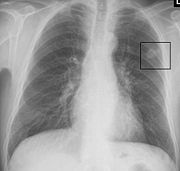

| Cross section of a human lung. The white area in the upper lobe is cancer; the black areas indicate that the patient was a smoker. | |

Performing a chest x-ray is the first step if a patient reports symptoms that may be suggestive of lung cancer. This may reveal an obvious mass, widening of the mediastinum (suggestive of spread to lymph nodes there), atelectasis (collapse), consolidation (pneumonia), or pleural effusion. If there are no x-ray findings but the suspicion is high (such as a heavy smoker with blood-stained sputum), bronchoscopy and/or a CT scan may provide the necessary information. Bronchoscopy or CT-guided biopsy is often used to identify the tumor type.